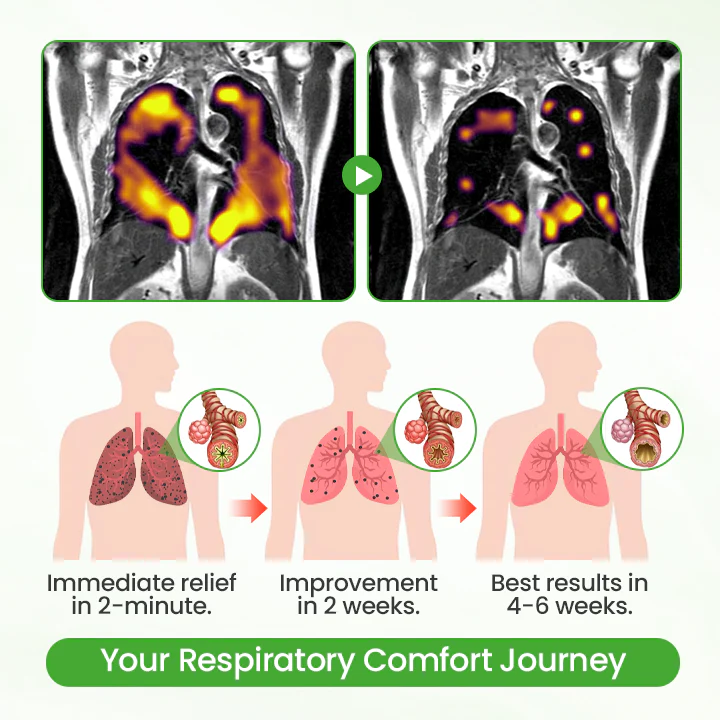

Your Respiratory Comfort Journey: What to Expect

Unlike traditional supplements that take hours to work, Timilk® HerbaAir delivers a clear comfort timeline. Within 2 minutes, you’ll feel significant soothing relief as mullein extract makes direct contact with your respiratory tissues. After 2 weeks of consistent use, persistent coughing and chest tightness begin to fade noticeably. By 4 weeks, you’ll experience sustained respiratory comfort improvement – breathing freely again. This progressive support works with your body’s natural processes for long-term wellness, not just temporary relief.

Real-World User Study Results

94.2% of users felt immediate relief within 2 minutes of first use, far faster than oral supplements

89.7% of users breathed significantly smoother within 2 minutes after use, and the feeling of chest tightness and breathlessness disappeared

91.8% of users had a significant reduction in cough after 4-8 weeks of continuous use, and most of the chronic cough disappeared completely

96.1% of users believe that nasal inhalation is more effective than all oral supplements and are reluctant to return to traditional products